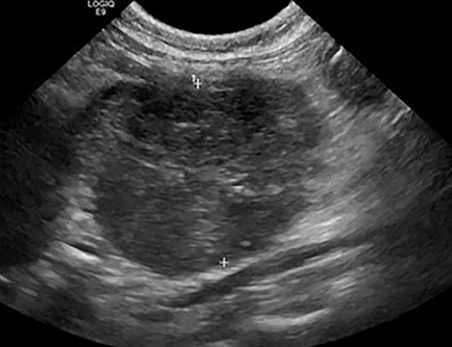

초음파 영상이나 여타 증상들이 상당부분 림프종을 의심하게끔 하는 양상으로 변하기 때문에 림프종으로 미리 포기해 버리는 수가 있을 수 있기에 주의가 필요할듯 하다.

세포 검사에서 확연하게 드러나는것은 아니라 특수 염색이 필요할 수도 있으니

림프종으로 생각되더라도 꼭 PCR 검사를 해볼 필요가 있는 질환이다.